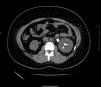

The patient also required frequent renal imaging in the form of CT KUBs and US kidneys in view of recurrent nephrolithiasis over the past 15 years and these imaging tests highlight the persistent significant bilateral kidney stone burden of the patient despite being treated for cystinuria and maintaining optimal alkaline urine pH levels (Fig. 1).

Non-contrast CT KUB which shows a swollen left kidney secondary to a stone with maximal size of 2.0cm in the left PUJ as well as multiple small stones in the right lower calyces of the kidney and left middle and lower calyces. This highlights the patient's significant stone burden despite being on optimal treatment for cystinuria.